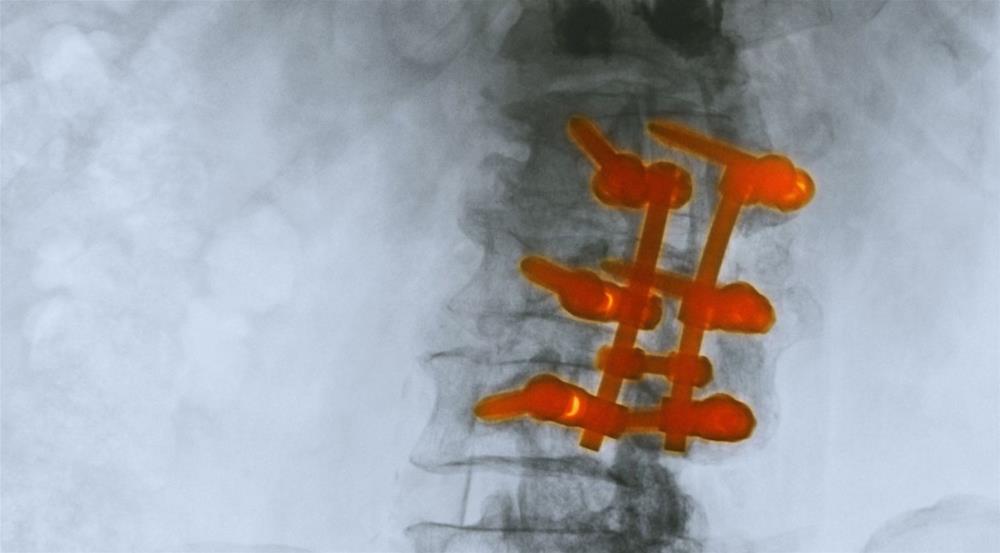

There are various problems that bone grafting can address, such as bone fractures, damaged joints, bones suffering from trauma that did not heal properly, lost bones due to infection or disease, and giving better support around an implanted device by growing bones. If the treatment is successful, patients are left with completely regenerated bones that are well and fully integrated in its surrounding region.

Not all transplanted grafts are the same; there are three different kinds of bone grafts that can be transplanted: an autologous bone graft is one that is taken from a person’s own body; an allograft is one that comes from a donor; and an artificial bone graft is one that is made in the lab. After bone grafts are transplanted, they are eventually reabsorbed into the body; thus, bone and graft become one. Sometimes, the body rejects the transplant, causing complications; as with any other kind of transplant, you are never fully sure that the body will accept it. However, this procedure does have a high success rate and numbers show that bone graft procedures are on the rise, meaning that they are an effective treatment option, which is why medical researchers are investing time and effort in finding new ways to improve bone grafting.